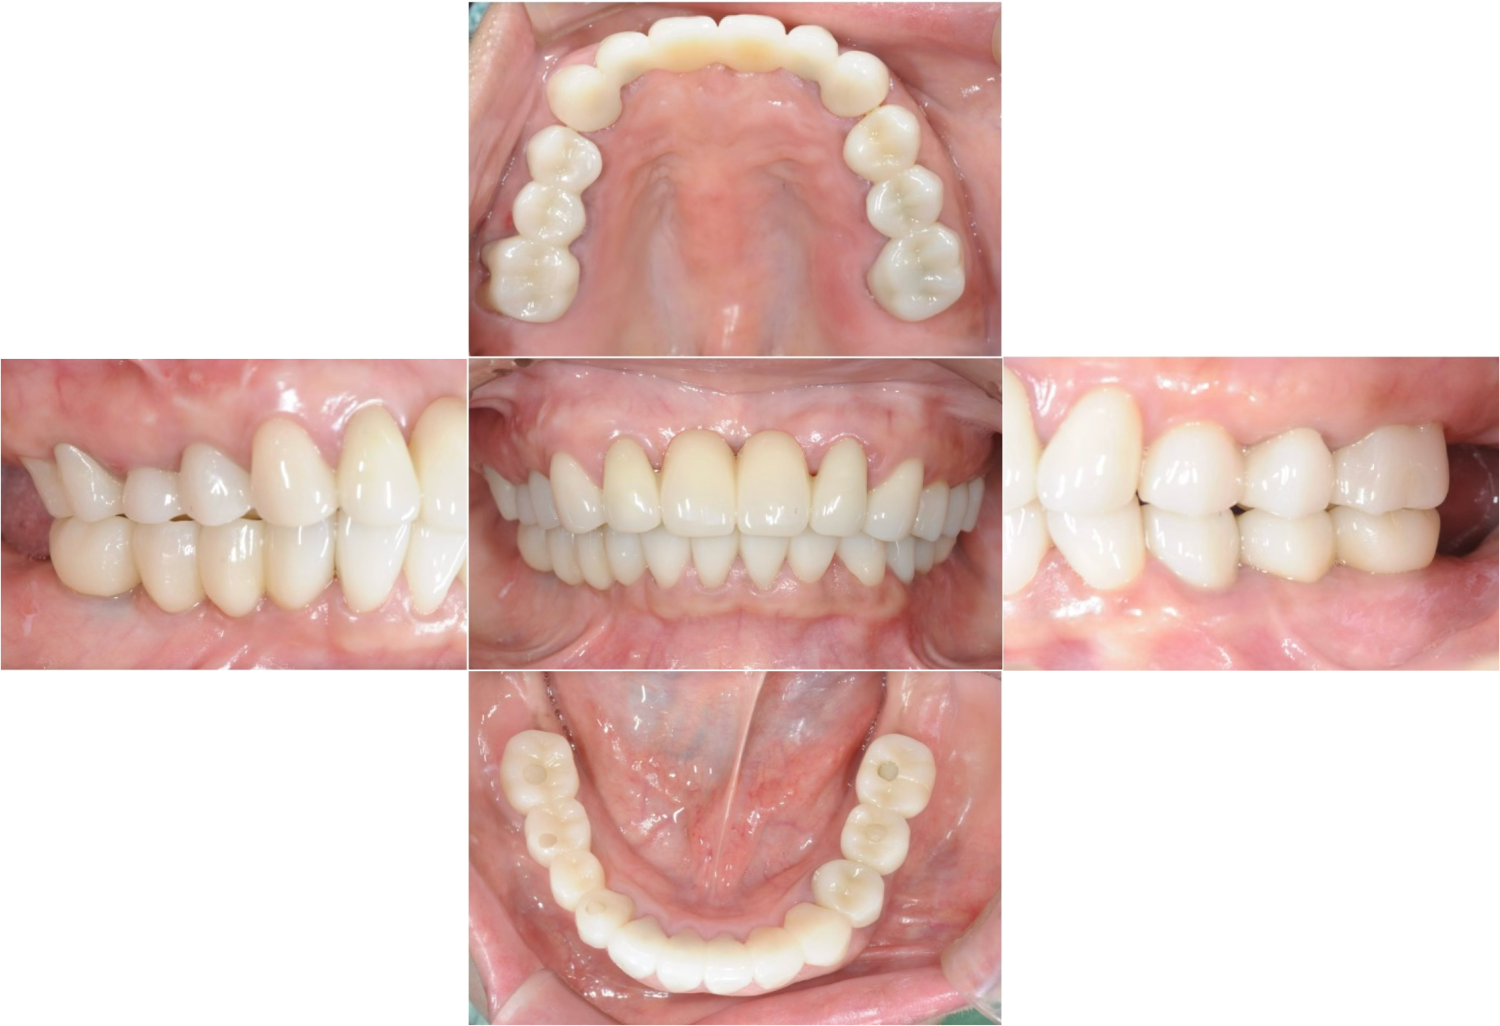

| 主訴 | 全顎治療希望、下の奥の歯が無いので全く噛めない。綺麗で噛めるようになりたい |

| 治療内容 | 下顎臼歯部欠損放置のため、臼歯部においてスペースがないため、全顎治療を行い咬合再構成を行う。 早期においてインプラント治療、咬合関係を模索した後、全顎にわたりセラミックによる補綴治療、その後メインテナンスに移行 |

| 想定されたリスク | 食いしばり(パラファンクション)によるセラミックの破折、歯の破折 |